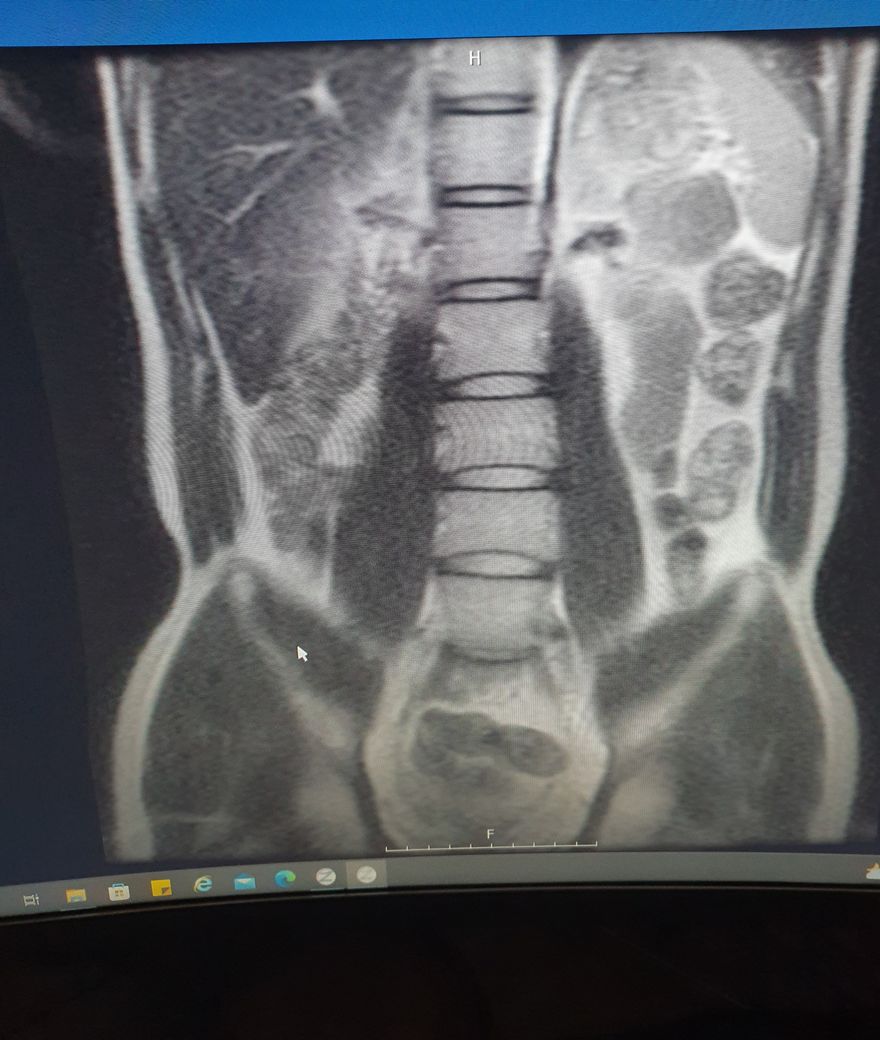

허리mri사진좀 봐주세요 ㅠㅠ만성통증

엉덩이 위쪽에전반적으로 뻐근한통증이 있습니다..ㅠ

하지 저림증상은 없구요...5번1번이 굉장히 좁은거 같은데..많이 안좋나요??

MRI로 보면 너무너무 건강한 허리입니다.

요추 5번 천추 1번 사이는 다른 요추들 사이의 디스크보다 당연히 좁아보일 수 있습니다.

지금 증상은 디스크 내장증 증상일 가능성이 있으며 요추 전만 자세만 잘 취해주시면 금방 좋아지실겁니다.